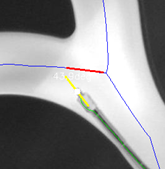

Now all the foundational data required for the interventional robot’s pose state perception have been obtained. Starting from the detected robot’s head point, and trace back 40 pixels for linear fitting, the robot’s direction vector is obtained. By overlaying vascular and robot skeletons, the algorithm locates the point on the vascular skeleton nearest to the robot’s head, then a 40-pixel (±20 pixels) segment of the skeleton around this point is extracted and fitted to obtain the vessel’s direction vector (Fig. 7). Both vectors are represented by their start, center, and end points.

Refer to caption

Figure 7: Image of fitted lines

The robot’s pose perception is then conducted from two aspects: relative position, and quantifying the posture through angles. The key parameters (Fig. 8) include: a) cross products between vascular vector and robot’s front/tail ends (cheadsubscript𝑐headc_{\text{head}}italic_c start_POSTSUBSCRIPT head end_POSTSUBSCRIPT/ctailsubscript𝑐tailc_{\text{tail}}italic_c start_POSTSUBSCRIPT tail end_POSTSUBSCRIPT); b) absolute values of cross products, representing distances to the vascular centerline (dheadsubscript𝑑headd_{\text{head}}italic_d start_POSTSUBSCRIPT head end_POSTSUBSCRIPT/dtailsubscript𝑑taild_{\text{tail}}italic_d start_POSTSUBSCRIPT tail end_POSTSUBSCRIPT); c) XOR of cross product signs, indicating whether centerline crossing (s𝑠sitalic_s); d) angle between robot and vessel direction vectors (θ𝜃\thetaitalic_θ).

Figure 8: Key parameters of interventional robot